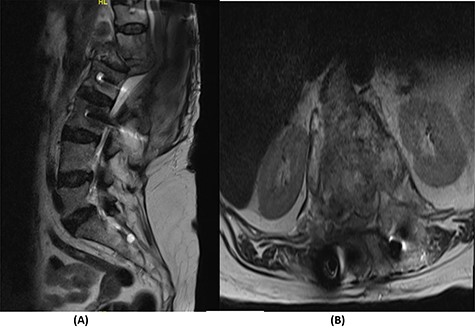

Radiological and laboratory investigations for possible malignancy or infection were done, and results were negative for malignancy. Erythrocyte sedimentation rate (ESR) was 50 mm/h and C-reactive protein (CRP) level was 38 mg/l. A magnetic resonance imaging (MRI) scan of the spine with contrast showed a significant pathological fracture of L1 along with spinal cord compression (Fig. 1). The patient underwent posterior spinal decompression of T12–L1 and pedicle instrumentation of T11–L3 with tissue and bone biopsy.

(A) T2-weighted sagittal lumbar spine MRI demonstrating a pathological fracture of L1 with spinal canal and neural foramina stenosis and cord edema and epidural and prevertebral soft tissue components. (B) T2-weighted axial lumbar spine MRI of the corresponding level of L1 vertebral body.